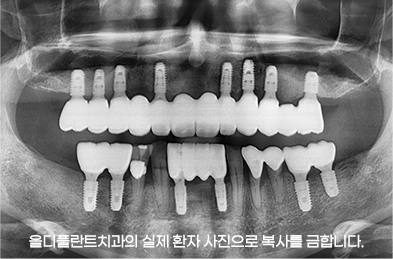

결과로 보여드리는 의료진의 노하우

- 24.07

* 임플란트 시술 시 교합이상, 신경손상, 염증 등의 부작용이 발생할 수 있습니다.

* 개인의 구강 및 치아상태에 따라 치료방법과 수가가 변동될 수 있습니다.

* 해당 사례는 의료법 제56조 2항을 준수하여 작성되었습니다.

* 본원에서 진료받은 환자이며 전후 사진의 인물이 동일인임을 밝힙니다.